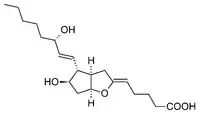

Biosynthesis of Prostanoid

Cyclooxygenase (COX) catalyzes the conversion of the free essential fatty acids to prostanoids by a two-step process. In the first step, two molecules of O2 are added as two peroxide linkages and a 5-member carbon ring is forged near the middle of the fatty acid chain. This forms the short-lived, unstable intermediate Prostaglandin G (PGG). One of the peroxide linkages sheds a single oxygen, forming PGH. (See diagrams and more detail at Cyclooxygenase). All other prostanoids originate from PGH (as PGH1, PGH2, or PGH3).

Figure 1 shows how PGH2 (derived from Arachidonic acid) is converted:

- By PGE synthetase into PGE (which in turn is converted into PGF)

- By PGD synthetase into PGD

- By Prostacyclin synthase into prostacyclin (PGI2)

- By Thromboxane synthase into thromboxanes

The three classes of prostanoids have distinctive rings in the center of the molecule. They differ in their structures. The PGH compounds (parents to all the rest) have a 5-carbon ring, bridged by two oxygens (a peroxide.) The derived prostaglandins contain a single, unsaturated 5-carbon ring. In prostacyclins, this ring is conjoined to another oxygen-containing ring. In thromboxanes the ring becomes a 6-member ring with one oxygen.

Leukotrienes pathway

Leukotrienes are synthesized in the cell from arachidonic acid by 5-lipoxygenase. The catalytic mechanism involves the insertion of an oxygen moiety at a specific position in the arachidonic acid backbone. The lipoxygenase pathway is active in leukocytes, including mast cells, eosinophils, neutrophils, monocytes, and basophils. When such cells are activated, arachidonic acid is liberated from cell membrane phospholipids by phospholipase A2, and donated by the 5-lipoxygenase-activating protein (FLAP) to 5-lipoxygenase. 5-Lipoxygenase (5-LO) uses FLAP to convert arachidonic acid into 5-hydroperoxyeicosatetraenoic acid (5-HPETE), which spontaneously reduces to 5-hydroxyeicosatetraenoic acid (5-HETE). The enzyme 5-LO acts again on 5-HETE to convert it into leukotriene A4 (LTA4), an unstable epoxide. In cells equipped with LTA4 hydrolase, such as neutrophils and monocytes, LTA4 is converted to the dihydroxy acid leukotriene LTB4, which is a powerful chemoattractant for neutrophils acting at BLT1 and BLT2 receptors on the plasma membrane of these cells. In cells that express LTC4 synthase, such as mast cells and eosinophils, LTA4 is conjugated with the tripeptide glutathione to form the first of the cysteinyl-leukotrienes, LTC4. Outside the cell, LTC4 can be converted by ubiquitous enzymes to form successively LTD4 and LTE4, which retain biological activity. The cysteinyl-leukotrienes act at their cell-surface receptors CysLT1 and CysLT2 on target cells to contract bronchial and vascular smooth muscle, to increase permeability of small blood vessels, to enhance secretion of mucus in the airway and gut, and to recruit leukocytes to sites of inflammation. Both LTB4 and the cysteinyl-leukotrienes (LTC4, LTD4, LTE4) are partly degraded in local tissues, and ultimately become inactive metabolites in the liver.